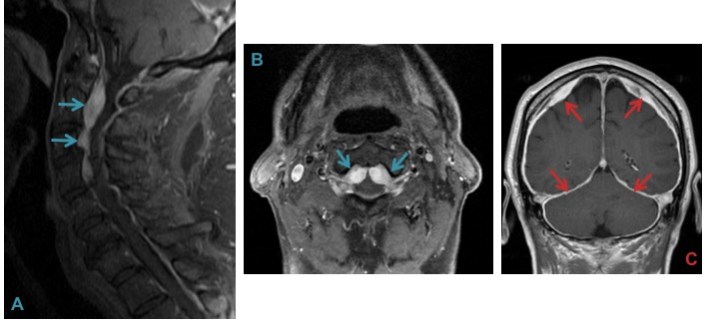

g) Retro-odontoid cyst – can cause mass effect on cervico-medullary junction. Doesn’t show contrast enhancement.

Epidural venous engorgement and dural thickening (A & B) from profound intracranial hypotension can often mimic a mass lesion. Clue to the diagnosis is diffuse pachymeningeal enhancement (C) seen on the brain MRI.